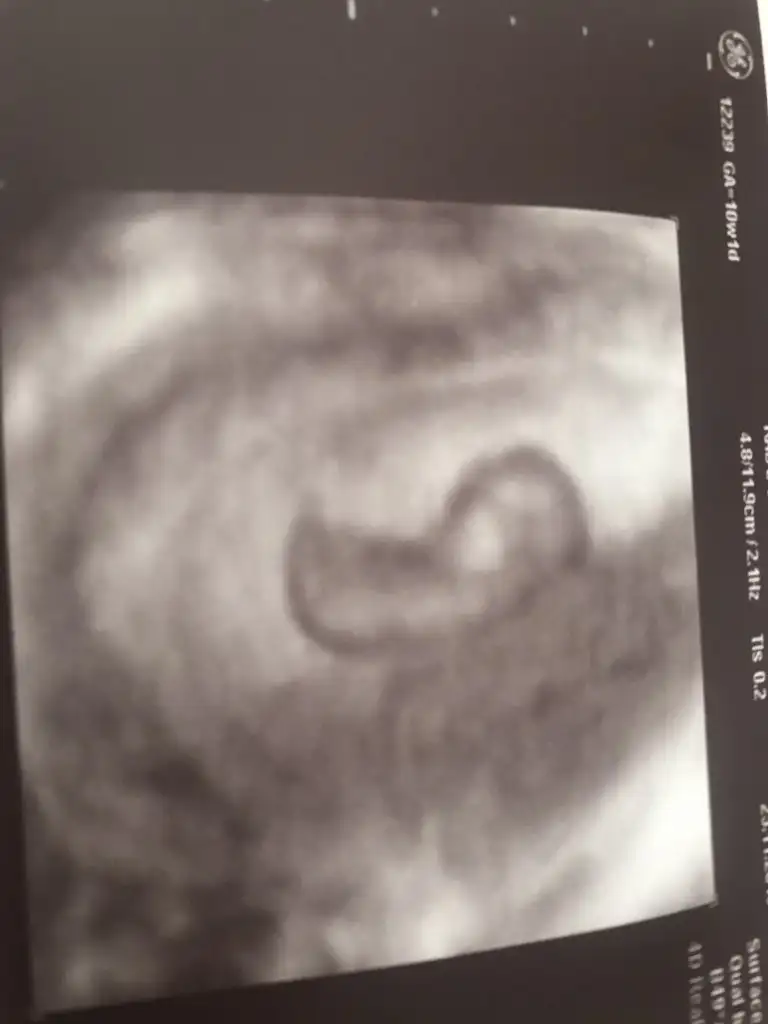

Tekrar bakar mısınız

Eklentiler

• 7DCC7290-676B-413C-A2DB-9887E57E554C.webp

7DCC7290-676B-413C-A2DB-9887E57E554C.webp

10,3 KB · Görüntüleme: 33

• F9E5B784-A344-4937-A1EA-FC6760B883FD.webp

F9E5B784-A344-4937-A1EA-FC6760B883FD.webp

8,8 KB · Görüntüleme: 40